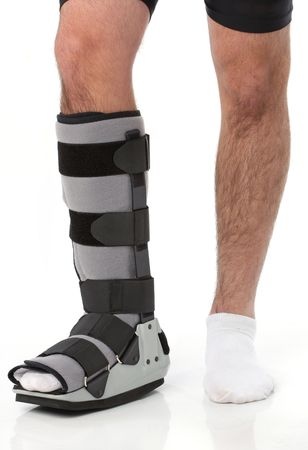

Braces: Your surgeon will determine what kind of protective brace that you will have to wear throughout the different phases of the healing/rehabilitation process. Initially, the surgeon requires a period of immobility for several weeks. This entails wearing a cast for that period of time. As the patient progresses through the post-op period, the protective bracing becomes less cumbersome and allows for more motion and enables you to begin a formal Physical Therapy program. In most cases the patient will be required to wear a form of protective bracing for 2-3 months. When you return to high-level activity, you might be asked to wear a brace that will aid in supporting the involved ankle and help avoid reinjuring the ankle. The braces help support the ankle throughout the rehabilitation process until the muscles are strong enough to provide dynamic support to the joint.

The patient will begin a formal Physical Therapy program when the cast is removed and the patient is placed in a protective “boot.” Prior to that, the patient can perform core and upper extremity exercises. The goal of formal therapy is to regain normal, pain-free motion in all planes and re-establish strength and normal neuro-muscular activity throughout the involved leg. Some weight-bearing forces through the healing bone will stimulate more bone production and healing. The Physical Therapist can teach the patient proper activities and exercises that will aid in the return of their “normal” ankle function.